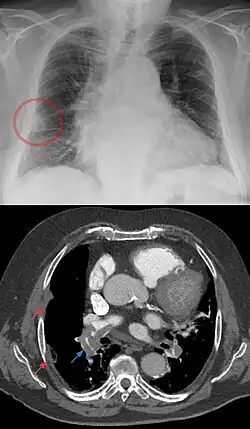

Hampton hump

Hampton hump oder Hampton’s hump ist die englischsprachige Bezeichnung für eine kuppelförmige, pleuraständige Verdichtung im Röntgenbild, die Ausdruck eines peripheren Lungeninfarktes im Rahmen einer Lungenembolie ist. Auch andere Ursachen für einen Lungeninfarkt wie z. B. eine Aspergillose sind denkbar, jedoch weit seltener.

Ein Hampton hump ist somit neben dem Westermark-Zeichen und dem Fleischner-Zeichen ein Röntgenzeichen für eine Lungenembolie. Alle genannten Zeichen sind aber nicht zwingend vorhanden, sondern kommen im Gegenteil eher selten vor.